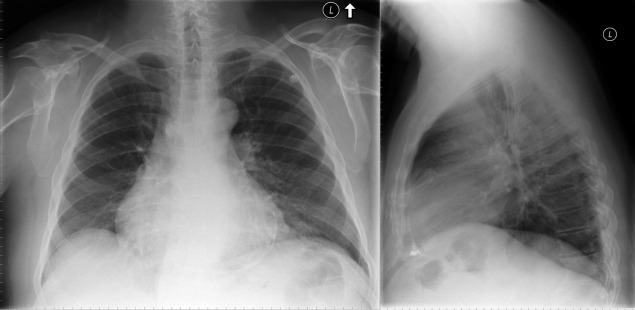

A calcified ventricular aneurysm is seen as a fine dense line when viewed on edge and is consistent with an old transmural infarction. On the frontal chest radiograph, an anterolateral, or apical, calcified aneurysm may be visible. Rarely, a calcified septal aneurysm may be seen on a lateral chest radiograph. Myocardium may calcify following traumatic injury as well as postinfarction.